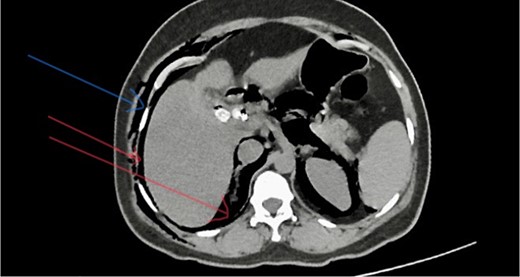

She has undergone a semi-elective ERCP in a semi-prone position, under sedation with propofol target-controlled infusion. Major papillae identified with side viewing endoscopy. Guidewire was inserted into CBD, and a cholangiogram was done. It showed dilated CBD up to 1.3 cm, mild dilated hepatic ducts, and a large radiolucent area in the distal CBD (around 1.5 cm). Sphincterotomy was done with a sphincterotome, and the ampulla was dilated up to 1.5 cm with a balloon dilator. Then, a balloon retrieval was attempted and failed, probably due to a stone sticking to the CBD wall. Then, a mechanical lithotripter was used to break the stone, but it failed, damaging the instrument. During the procedure, her oxygen saturation dropped to 75–80%, and she developed surgical emphysema in the face, neck, and upper chest region. In addition, she developed abdominal distention as well. Immediately, she underwent CBD stenting with a 12-cm, 10 French Gauge double pigtail biliary stent and changed her position to supine. Then, she was intubated with rapid sequence induction, and a nasogastric tube was inserted and transferred to the surgical intensive care unit. Post-ERCP, non-contrast computed tomography (NCCT) of the abdomen and chest showed extensive pneumo-peritoneum and retroperitoneal gas with subcutaneous emphysema (Figs 2 and 3). There was no evidence of air leakage on NCCT and no clinical features of peritonitis on subsequent days. So she was managed non-surgically with nasogastric tube (NG), nil by mouth, intravenous fluids with intravenous antibiotics. Clear fluid was started after 24 hours slowly via NG.

Post-ERCP NCCT abdomen shows pneumo-retroperitoneum (red arrow).